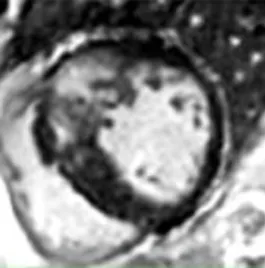

Contrast-free “synthetic LGE” has been developed through the use of generative adversarial networks (GANs). Two leading techniques have been developed: “virtual native enhancement (VNE)” (1, 2), which has native T1 maps and cine MRI as inputs, and has been applied to chronic myocardial infarction (MI) (2) and HCM (1), and “cine-generated enhancement (CGE)”, which identifies LGE from cine MRI only and has been applied to acute MI (16). Both techniques demonstrated potential to detect the respective pathologies tested. Furthermore, infarct VNE has been validated ex-vivo in porcine models (2).

The success of the synthetic LGE methods suggests that enough information to identify scar or fibrosis is likely to exist in contrast-free images which may be conceptually challenging for CMR operators. This scar identification may be suitable for AI only and difficult for human operators. The propensity of GANs for hallucinations makes it critical to validate this concept in large diverse datasets, especially in the presence of poor image quality (often degraded due to patient factors) found in the clinical arena (1, 32).

An alternative to GANs to synthesise LGE from cine CMR is the analysis of local motion biomarkers (such as displacements and local strains) in cine MRI. Here, scar is identified due to its different biomechanical properties (e.g., stiffness) when compared to healthy myocardium. In a small study, a motion-feature learning framework based on long-short term memory (LSTMs) applied to cine CMR identified myocardial infarction, achieving a high accuracy when evaluated against the manual segmentation ground-truth (21).

Despite modest patient numbers used to train these models (1, 2, 16), initial proof-of-concept work could support contrast-free identification of scar. Ruling out scar may be useful to negate the use of GBCA in patients with low pre-test probability. Further, as opposed to replicating LGE, these techniques may even provide incremental information, giving additional trust to LGE findings or even detecting subtle abnormalities missed by LGE alone.